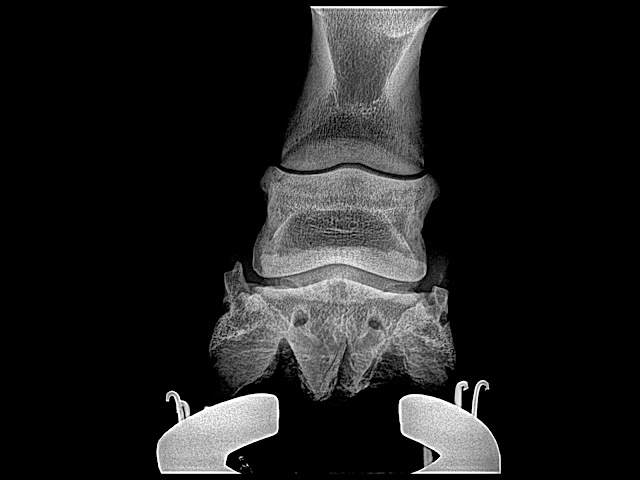

This is a case with navicular bone changes that had responded to increase in palmar angle and reduction in digital breakover but was not consistently going sound. Dr. Redden applied an aluminum rocker rail. Look at the TSA and the distance the navicular is from the proximal p2 between the pre and post shoe radiographs.

This case had an acute bout of laminitis about 6 months ago. Venograms show that circumflex is above the apex of coffin bone and compressed tightly to tip of coffin bone as well. Dorsal lamellar zone on the right front is broken and a void of contrast is present at coronary plexus. No solar papillae are evident even at an increased to 20 degree palmar angle which should unload DDFT by 60 percent. Treatment included derotational shoeing followed by a deep digital flexor tenotomy.